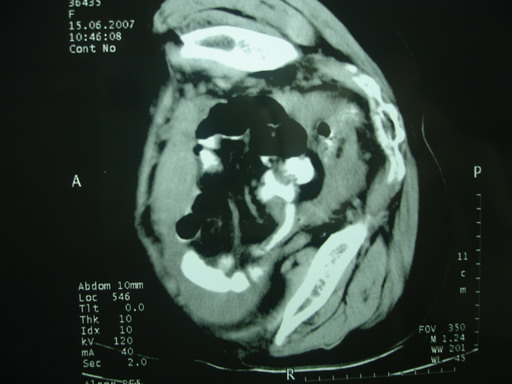

女,70岁,自述锻炼时牵拉导致左下腹疼痛,后疼痛加剧,发现包块10天,家属说其他检查,无法热,大便正常,一般情况差,痛苦面容,左下腹压痛明显,口服造影剂后腹泻,钡灌肠降结肠迂曲粘膜未见异常。抗炎治疗一周后诉症状减轻。

以下图考虑是何病?谢谢!

大网膜血肿?建议增强进一步检查。

外伤性大网膜积液、血肿?穿刺一下吧!

盆腔附件区不规则软组织密度影,与下腹部异常密度影相联,建议进一步检查除外妇科疾患!

肠系膜血肿.